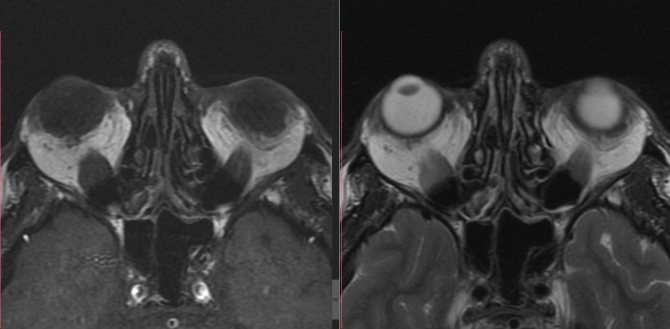

В основе патологического процесса ЭОП лежит поражение мягких тканей орбиты на фоне нарушенной функции щитовидной железы. Характер и степень поражения щитовидной железы при этом могут быть различными. При длительном наблюдении за 925 больными с ЭОП в возрасте от 14 до 77 лет (средний возраст 42 года) дисфункция щитовидной железы была обнаружена у 81,5% больных, из них у 73,4% – гиперфункция, у 8,1% – гипофункция. У 18,5% больных на фоне выраженной картины ЭОП эндокринологи констатировали эутиреоидное состояние. Однако хорошо известно, что глазные симптомы могут появиться как до клинических проявлений гипертиреоза, так и спустя 15 и даже 20 лет после его возникновения. И действительно, около 78% наших больных к моменту обращения к офтальмологу длительное время получали медикаментозное лечение по поводу гипертиреоза. В то же время офтальмологам известны случаи появления ЭОП у больных, перенесших операцию на щитовидной железе. Чаще это происходит в случаях тотального удаления щитовидной железы. Ввиду отсутствия временной корреляции между появлением симптомов ЭОП и признаков дисфункции щитовидной железы, появившийся в последние годы термин “эутиреоидная болезнь Грейвса” [2], вероятно, будет пересмотрен. Патогенез На протяжении многих лет дискутируется вопрос о том, что является объектом первичной атаки патологического процесса в орбите: ее клетчатка или экстраокулярные мышцы. Вопрос о первичной мишени иммунного ответа до настоящего времени не решен. Большинство исследователей считают, что ретробульбарная клетчатка является первоначальной антигенной мишенью при ЭОП [3, 4]. Именно на перимизиальных фибробластах, эндотелии сосудов жировой ткани, а не на экстраокулярных миоцитах была обнаружена экспрессия маркеров ЭОП (теплошоковых протеинов 72 кД, HLA-DR-антигенов, межклеточных молекул адгезии ICAM-1, молекул эндотелиальной адгезии лимфоцитов). Образование адгезирующих молекул, экспрессия HLA-DR приводят к инфильтрации ретробульбарных тканей иммуноцитами и запуску иммунных реакций [2, 4]. Причины избирательного поражения мягких тканей орбиты, возможно, кроются в следующем. Не исключено, что фибробласты орбиты имеют собственные антигенные детерминанты, которые и распознает иммунная система [5, 6]. Предполагается, что фибробласты орбиты (преадипоциты), в отличие от фибробластов других локализаций, способны к дифференцировке в адипоциты in vitro [3, 7]. Эндокринная офтальмопатия – аутоиммунное заболевание, проявляющееся патологическими изменениями в мягких тканях орбиты с вторичным вовлечением глаза. В настоящее время существуют две теории патогенеза ЭОП. Согласно одной из них, в качестве возможного механизма рассматривают перекрестное реагирование антител к щитовидной железе с тканями орбиты, наиболее часто встречающееся при диффузном токсическом зобе (ДТЗ). На это указывает частое сочетание (в 90% случаев) ЭОП и ДТЗ [8] и частое одновременное их развитие, уменьшение выраженности глазных симптомов при достижении эутиреоза. У больных с ДТЗ и ЭОП отмечается высокий титр антител к рецептору тиреотропного гормона (ТТГ), который снижается на фоне тиреостатической терапии [3, 9]. По мнению других авторов, ЭОП – самостоятельное аутоиммунное заболевание с преимущественным поражением ретробульбарных тканей. В 5–10% случаев при ЭОП не выявляется дисфункции щитовидной железы [10]. При ЭОП выявляются антитела к мембранам глазодвигательных мышц (с мол. массой 35 и 64 кД; антитела, стимулирующие рост миобластов) [11, 12], фибробластам и орбитальной клетчатке. Причем антитела к глазодвигательным мышцам выявляются не у всех больных, в то время как антитела к орбитальной клетчатке можно считать маркером ЭОП [3, 13]. На рис.1 представлен патогенез ЭОП [13, 14]. Под действием пусковых механизмов, возможно, вирусной или бактериальной инфекции (ретровирусы, Yersenia enterocolitica), токсинов, курения, радиации, стресса у генетически предрасположенных лиц в мягких тканях орбиты экспрессируются аутоантигены. При ЭОП имеется антигенспецифический дефект Т-супрессоров. Это делает возможным выживание и размножение клонов Т-хелперов, направленных против аутоантигенов щитовидной железы и мягких тканей орбиты. В ответ на появление аутоантигенов Т-лимфоциты и макрофаги, инфильтрируя ткани орбиты, высвобождают цитокины. Цитокины индуцируют образование молекул основного комплекса гистосовместимости II класса, теплошоковых протеинов и адгезивных молекул. Цитокины стимулируют пролиферацию ретробульбарных фибробластов, выработку коллагена и гликозаминогликанов (ГАГ). ГАГ с белками образуют протеогликаны, способные связывать воду и вызывать отек мягких тканей орбиты. При гипертиреозе дефект иммунологического контроля усугубляется: при декомпенсированном ДТЗ уменьшается количество Т-супрессоров. При ДТЗ снижается также активность естественных киллеров, что приводит к синтезу аутоантител В-клетками и запуску аутоиммунных реакций. Развитие ЭОП при гипотиреозе можно объяснить следующим образом. В норме трийодтиронин (Т3) ингибирует синтез ГАГ. При гипотиреозе в связи с дефицитом Т3 ингибирующий эффект уменьшается. Кроме того, высокий уровень ТТГ приводит к увеличению экспресии HLA-DR на тиреоцитах, что усиливает патологический процесс в орбитах [14]. Клиническая картина Клинические наблюдения за больными с ЭОП позволяют выделить три самостоятельных формы заболеваний: тиреотоксический экзофтальм, отечный экзофтальм и эндокринную миопатию. В ходе развития патологического процесса тиреотоксический экзофтальм может перейти в отечный экзофтальм, который может завершиться картиной эндокринной миопатии. При последних двух формах морфологически в экстраокулярных мышцах и орбитальной клетчатке в начале процесса наблюдают интенсивную клеточную инфильтрацию, на смену которой приходит стадия фиброза. Тиреотоксический экзофтальм Тиреотоксический экзофтальм встречается всегда на фоне тиреотоксикоза, чаще у женщин. Может быть односторонним. Сопровождается тремором рук, тахикардией, снижением массы тела, нарушением сна. Больные жалуются на раздражительность, постоянное чувство жара. Глазная щель у таких больных распахнута, хотя экзофтальма при этом нет, либо он не превышает 2 мм (рис. 2). Увеличение глазной щели происходит за счет ретракции верхнего века (мышца Мюллера – средний пучок леватора верхнего века находится в состоянии спазма). При тиреотоксическом экзофтальме больные редко мигают, характерен пристальный взгляд. Могут быть обнаружены и другие микросимптомы: симптом Грефе (при взгляде книзу появляется отставание верхнего века и обнажается полоска склеры над верхним лимбом), нежный тремор век при их смыкании, но веки смыкаются полностью. Объем движений экстраокулярных мышц не нарушен, глазное дно остается нормальным, функции глаза не страдают. Репозиция глаза не затруднена. Использование инструментальных методов исследования, включая компьютерную томографию и ядерно-магнитный резонанс, доказывает отсутствие изменений в мягких тканях орбиты. Описанные симптомы исчезают на фоне медикаментозной коррекции дисфункции щитовидной железы. Отечный экзофтальм Отечный экзофтальм появляется как у женщин, так и у мужчин, возникает на фоне гипертиреоза (чаще), гипотиреоза или при эутиреоидном состоянии. Процесс, как правило, двусторонний, но поражение обоих глаз чаще происходит разновременно, интервал иногда составляет несколько месяцев. Начало патологического процесса знаменуется частичным интермиттирующим птозом: верхнее веко по утрам несколько опускается, к вечеру оно занимает нормальное положение, но при этом сохраняется тремор закрытых век. Глазная щель на этой стадии закрывается полностью. В дальнейшем частичный птоз быстро переходит в стойкую ретракцию верхнего века. В механизме ретракции принимают участие три фактора: спазм мышцы Мюллера (на первом этапе), который может быть кратковременным, а затем становится постоянным; постоянный спазм мышцы Мюллера приводит к повышению тонуса верхней прямой мышцы и леватора; длительный повышенный мышечный тонус вызывает возникновение контрактуры в мюллеровской и верхней прямой мышцах. В этот период развивается стационарный экзофтальм. Иногда появлению экзофтальма предшествует мучительная диплопия, обычно с вертикальным компонентом, так как первоначально страдает нижняя прямая мышца. Описанная картина представляет собой компенсированную стадию процесса (рис. 3). Появление белого хемоза у наружного угла глазной щели и вдоль нижнего века, а также возникновение невоспалительного отека периорбитальных тканей и внутриглазной гипертензии характеризуют собой стадию субкомпенсации. Морфологически в этот период находят резкий отек орбитальной клетчатки, интерстициальный отек и клеточную инфильтрацию экстраокулярных мышц (лимфоцитами, плазмоцитами, тучными клетками, макрофагами и большим количеством мукополисахаридов), последние оказываются резко увеличенными в 6–8, иногда в 12 раз (рис. 4). Экзофтальм нарастает достаточно быстро, репозиция глаза становится невозможной, глазная щель не закрывается полностью. В месте прикрепления экстраокулярных мышц к склере появляются застойно полнокровные, расширенные и извитые эписклеральные сосуды, которые формируют фигуру “креста”. Симптом “креста” – патогномоничный признак отечного экзофтальма. Внутриглазное давление остается нормальным только при положении глаза прямо. При взгляде кверху оно повышается на 3–6 мм рт.ст. за счет сдавления глаза увеличенными плотными верхней и нижней прямыми мышцами. Этот признак типичен для ЭОП и никогда не встречается при опухолях орбиты. По мере нарастания патологического процесса ЭОП переходит в стадию декомпенсации, для которой характерно агрессивное нарастание клинических симптомов: экзофтальм достигает больших степеней, появляется несмыкание глазной щели за счет резкого отека периорбитальных тканей и век, глаз неподвижен, возникает оптическая нейропатия, которая может достаточно быстро перейти в атрофию зрительного нерва. В результате сдавления цилиарных нервов развивается тяжелейшая кератопатия или язва роговицы (рис. 5). Без лечения отечный экзофтальм по истечении 12–14 мес завершается фиброзом тканей орбиты, что сопровождается полной неподвижностью глаза и резким снижением зрения (бельмо роговицы или атрофия зрительного нерва). Эндокринная миопатия Эндокринная миопатия – процесс двусторонний, возникает чаще у мужчин на фоне гипотиреоза или эутиреоидного состояния. Заболевание начинается с диплопии, интенсивность которой нарастает постепенно. Диплопия обусловлена резкой ротацией глаза в сторону, ограничением его подвижности. Постепенно развивается экзофтальм с затрудненной репозицией (рис. 6). Другие симптомы, присущие отечному экзофтальму, отсутствуют. Морфологически у таких больных не находят резкого отека орбитальной клетчатки, но имеется резкое утолщение одной или двух экстраокулярных мышц, плотность которых резко повышена. Стадия клеточной инфильтрации очень короткая, и через 4–5 мес развивается фиброз. Лечение Лечение ЭОП проводится совместно офтальмологом и эндокринологом с учетом степени тяжести заболевания и нарушения функции щитовидной железы. Непременным условием успешного лечения является достижение эутиреоидного состояния. При гипотиреозе необходима заместительная терапия L-тироксином под контролем ТТГ. При гипертиреозе показано лечение тиреостатиками (тиамазол), которое проводят длительно (12–18 мес) под контролем общего анализа крови (лейкоциты, тромбоциты) и тиреоидных гормонов. Возможно сочетание тиреостатиков с L-тироксином по принципу “блокирую и замещаю”. При неэффективности консервативной терапии ДТЗ показано оперативное лечение, более предпочтительна тотальная тиреоидэктомия, так как у больных после неполного удаления щитовидной железы отмечается стойкое повышение антител к рецептору ТТГ, что может приводить к прогрессированию ЭОП. Необходимо помнить, что не только тиреотоксикоз, но и гипотиреоз любого генеза оказывает неблагоприятное влияние на течение ЭОП, причем ухудшение состояния глаз наблюдается при резком переходе от одного состояния к другому. Поэтому после оперативного лечения ДТЗ необходимо тщательно следить за уровнем тиреоидных гормонов крови и проводить профилактику и адекватное лечение гипотиреоза. Нередко клиническая картина ЭОП развивается у лиц без клинических признаков нарушения функции щитовидной железы. У этих больных при обследовании можно выявить субклинический гипертиреоз (нормальные уровни тиреоидных гормонов и сниженный уровень ТТГ), субклинический гипотиреоз (нормальные уровни тиреоидных гормонов и повышенный уровень ТТГ) или отсутствие патологических изменений. В последнем случае показано проведение пробы с тиролиберином (200–500 мкг внутривенно струйно) с определением уровня ТТГ исходно и через 30 мин после введения. В дальнейшем больной наблюдается у эндокринолога, проводится динамический контроль тиреоидного статуса. Лечение начинают при манифестации гипер- или гипотиреоза. Лечение ЭОП казуальное, симптоматическое и восстановительное. Казуальную терапию кортикостероидами назначают при субкомпенсации и декомпенсации процесса. Суточная доза их зависит от длительности заболевания, степени агрессивности глазных симптомов и составляет 40–80 мг/сут в пересчете на преднизолон. При резкой декомпенсации процесса, когда имеется угроза потери глаза, назначают дексаметазон по 4 мг каждые 4–8 ч в течение 3–4 сут или пульс-терапию по схеме. При давности заболевания, не превышающей 12–14 мес, стероидную терапию можно комбинировать с наружным облучением орбит. Симптоматическое лечение заключается в назначении пациенту антибактериальных капель, искусственной слезы, солнцезащитных очков и обязательно глазной мази на ночь. Восстановительное хирургическое лечение назначают при эндокринной миопатии с целью улучшения функций пораженных экстраокулярных мышц [1] или при резкой ретракции верхнего века для восстановления его нормального положения.